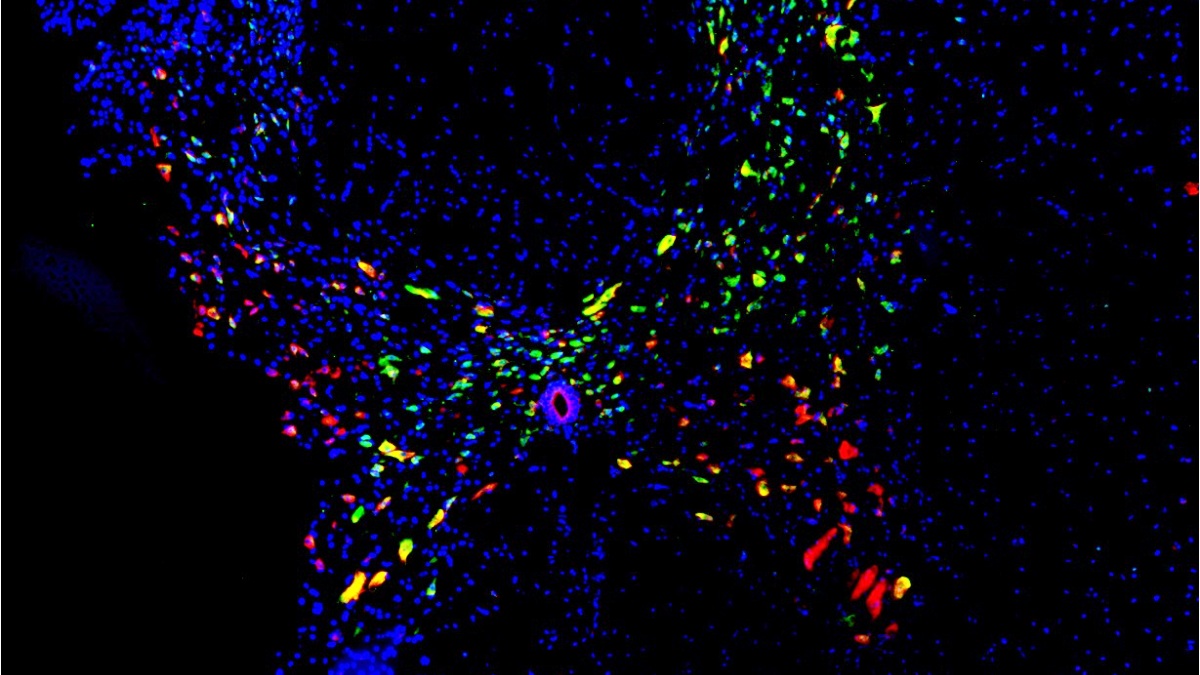

La imagen titulada ‘Rainbow Butterfly’ (Mariposa Arcoíris), realizada por el doctor David Reigada, biólogo del Grupo de Neuroprotección Molecular del Hospital Nacional de Parapléjicos de Toledo, ha ganado el concurso internacional de NeuroArt del mes de septiembre organizado por la empresa MBF BioScience.

La fotografía de David Reigada muestra una imagen correspondiente a un corte transversal de de la médula espinal de rata realizada a través de técnicas de microscopia de fluorescencia, ha informado la Junta en un comunicado.

En ella se observa la presencia del microRNA-138 (rojo), la diana terapéutica que estudia este equipo científico para reducir el daño neuronal derivado de una lesión medular. Esta molécula esta mayoritariamente presente en neuronas (verde y amarillo). Como en la médula espinal las neuronas se sitúan en el centro de la estructura, una zona llamada sustancia gris y que tiene forma de mariposa, la tinción exclusiva de sus neuronas hace que la mariposa destaque sobre el resto del tejido.

La imagen ‘Rainbow Butterfly’ ha obtenido 536 votos populares, obteniendo el tercer puesto en la categoría Jurado Popular, pero ha obtenido el premio especial del jurado a la mejor imagen del mes de septiembre, otorgado por un panel de expertos en imagen y técnicas microscópicas. El premio consiste en la posibilidad de la publicación de la imagen en la portada de la revista científica ‘Journal of Neuroscience Research’ si es elegida como la mejor fotografía del último semestre de 2021.

Esta imagen se ha obtenido en los microscopios pertenecientes a la Unidad de Investigación del Hospital Nacional de Parapléjicos y con el soporte técnico del personal del Servicio de Microscopía del centro.